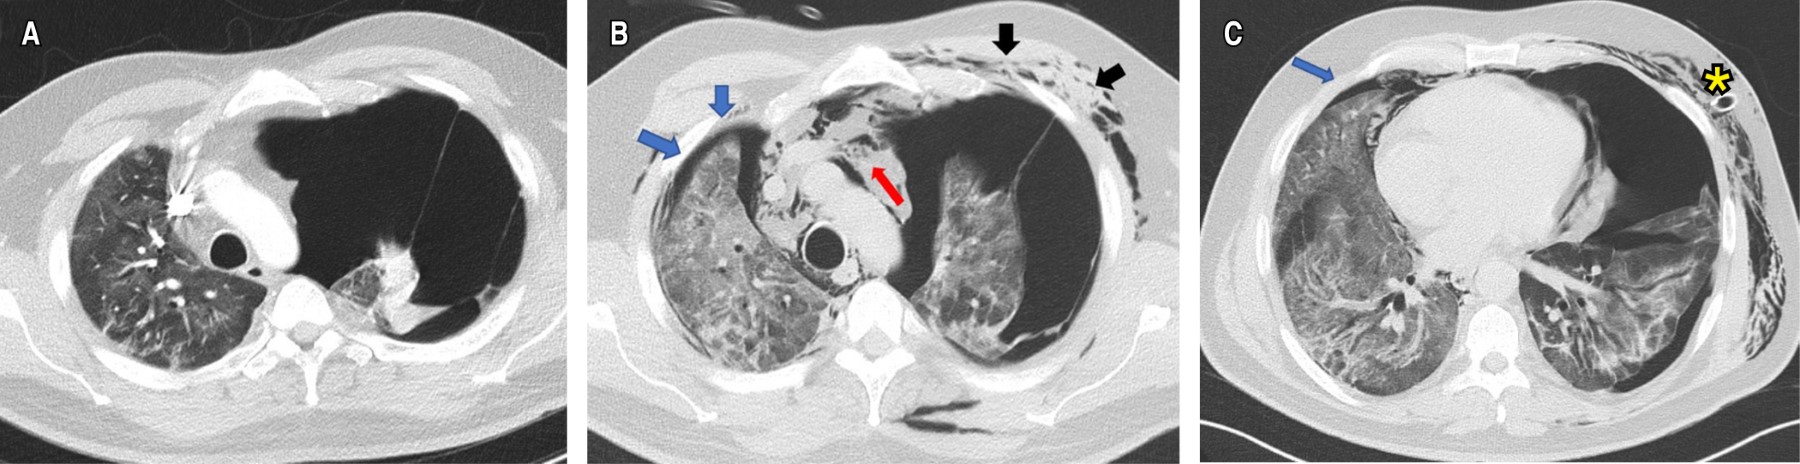

La angio-TC de tórax fue negativa para TEP, con evidencia de OVE del lado derecho y neumotórax contralateral que colapsaba 90% del pulmón (Figura 2A), por lo que se realizó una toracostomía cerrada izquierda de urgencia, sin lograrse la expansión pulmonar. Al tercer día de estancia hospitalaria, presentó deterioro de la oxigenación que requirió inicio de suplencia de oxígeno por cánula de alto flujo e ingresó a la unidad de cuidados intensivos (UCI) sin requerimiento de VM. La TC de alta resolución control (Figuras 2By C) demostró OVE, áreas de crazy paving de predomino derecho, neumotórax apical derecho pequeño (< 10%), neumomediastino y enfisema de los tejidos blandos del hemitórax izquierdo. Fue llevado a una segunda toracostomía cerrada a nivel apical izquierdo por cirugía de tórax, con persistencia del colapso pulmonar ipsilateral, por lo que se realizó decorticación y pleurectomía parietal por toracoscopia, con expansión satisfactoria. La patología reportó pleuritis crónica (Figura 3). Se indicó manejo conservador del neumotórax derecho, con expansión pulmonar en imágenes posteriores.

El reporte de imágenes previas en tórax aportado por el paciente no evidenciaba los hallazgos en el parénquima pulmonar durante esta hospitalización. Los estudios de autoinmunidad fueron negativos. Se consideró cuadro secundario a las complicaciones asociadas con neumonía severa por COVID-19. Por evolución favorable fue egresado a los 42 días de estancia hospitalaria. En la valoración a los 90 días (Tabla 1) se encontraba en rehabilitación pulmonar, continuaba con oxígeno a 1 L/min, refirió mejoría de la disnea, con una distancia recorrida por el test de caminata de seis minutos (TC6M) de 615 metros y un delta de SaO2 mayor de tres puntos. La TC control mostró lesión cicatricial en el lóbulo superior izquierdo por neumotórax y escasas OVE.